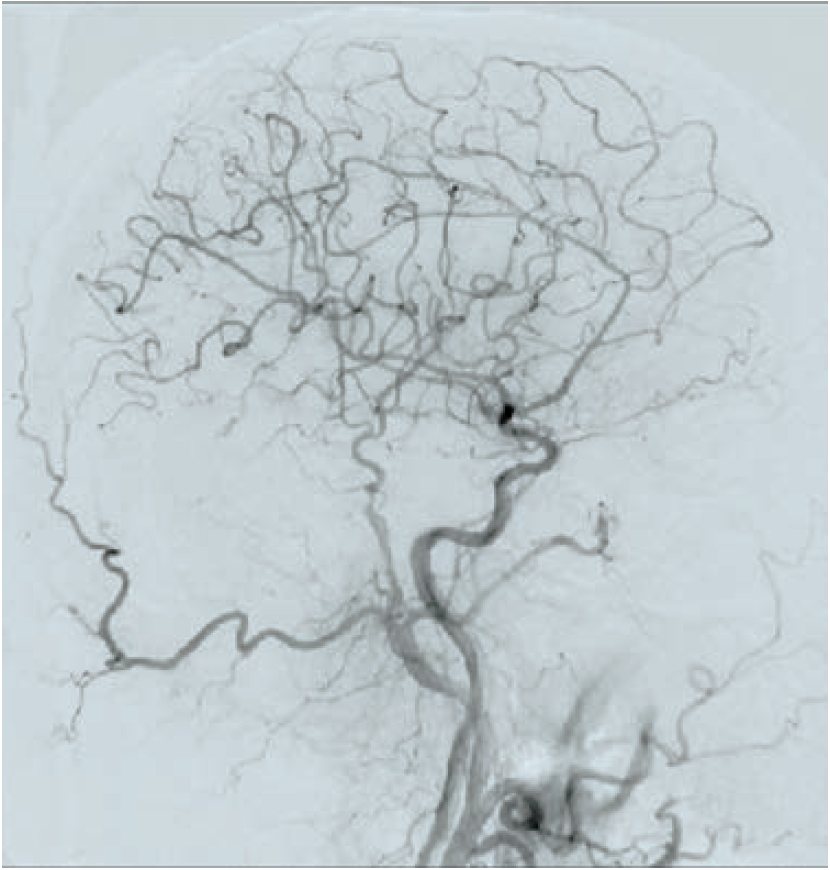

Following aseptic measures and under local anesthesia, a 7 French (Fr) right femoral access was obtained using a routine-length sheath. An .035-inch J-tip guide wire was then parked at the right common carotid artery (RCCA) using a 5 Fr Judkins right catheter, exchanged by a 7 Fr multipurpose guide. This was followed by advancement of a FilterWire EZ (Boston Scientific) across the ostial internal carotid artery stenosis, and deployed in the distal part of the extracranial ICA (Figure 2). After deployment of the FilterWire EZ, a direct stenting strategy was adopted to minimize thromboembolization. A 6 mm x 40 mm self-expanding stent was deployed at the RICA ostium (Figure 3). To our surprise, the view after stent placement showed zero flow into the distal RICA. (Figure 4) The reason appeared to be choking of the filter due to thromboembolization. The filter appeared to be overwhelmed by the volume of the debris captured. A 6 Fr Export catheter (Medtronic) was employed to suction debris from the distal ICA (Figure 5). We also administered pharmacotherapy using intra-arterial nitrate boluses and a weight-based tirofiban bolus. After these measures, there was fair flow into the distal ICA. During the period of no flow, the patient had transient hemispheric ischemic signs and an oropharyngeal airway was required, but his vitals remained stable. These symptoms rapidly resolved after establishment of ICA flow. After establishing blood flow, the proximal half of the stent that remained under-expanded was post dilated using a 4.5 mm noncompliant balloon at 12 atmospheres (Figure 6). Post dilatation, the angiographic view demonstrated good stent expansion and adequate distal flow (Figure 7). The distal protection device was then successfully removed using its retrieval sheath. The final DSA angiogram revealed excellent flow into the distal carotid (Figure 8A) and intracranial vasculature (Figure 8B), confirming no intracranial embolization. The guide was then safely removed over the .035-inch guide wire.